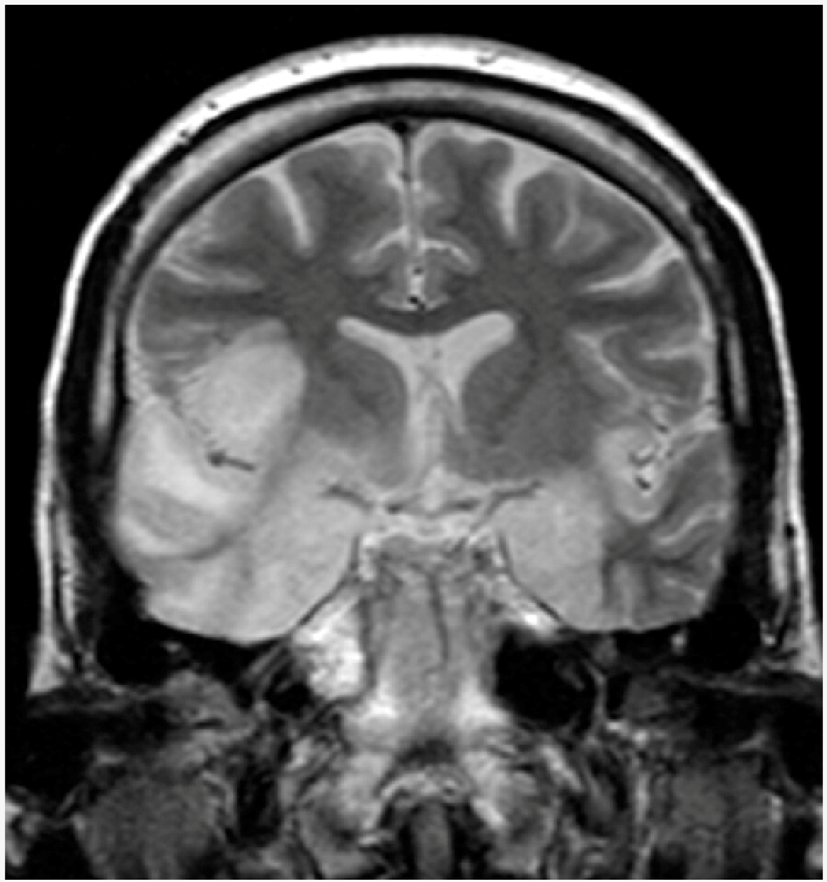

| Herpetic encephalitis or meningitis | Herpetic brain infection is thought to be due to the transmission of viruses from a peripheral site and the following reactivation of HSV-1, along the axon of the trigeminal nerve, to the brain. HSV is the most common cause of viral encephalitis. When the brain is infected, the virus shows a preference for the temporal lobe. HSV-2 is the most common cause of Mollaret’s meningitis, a type of recurrent viral meningitis. | ![]() 5. Herpes simplex encephalitis, licence CC BY 3.0, adapted with concession of Dr Laughlin Dawes—http://www.radpod.org/2007/03/24/herpes-simplex-encephalitis/. |